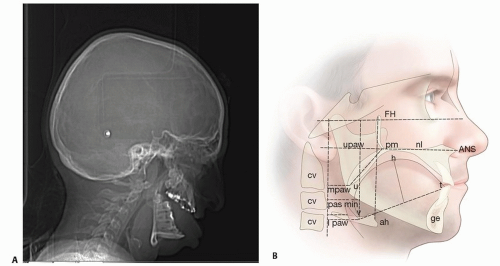

Cephalometric consideration for PAS (FIG 2A)

Nasopharynx

Pterygomaxillare (pm) to posterior pharyngeal wall (upaw)

Oropharynx

Tip of uvula (U) to posterior pharyngeal wall (mpaw)

Hypopharynx

Tongue base (V) to posterior pharyngeal wall (lpaw)

Plain film/CT exam findings (FIG 2B)

Shallow orbits

Hypertelorism

Exotropia

Bicoronal synostosis—brachycephaly

Choanal stenosis/atresia